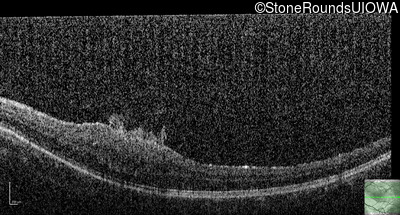

This 9 year old male was noted to have some crossing of his eyes at 2 months of age and the eye exam which followed identified a retinal lesion in the right eye. When he was six years old an epiretinal membrane was noted in his left eye. Two years later it was decided that it was a thin hamartoma in that eye as well. He underwent neuroimaging at age 7 which identified bilateral acoustic neuromas.

| Age at visit: 8 years |

| Age at visit: 10 years |

| Age at visit: 11 years |